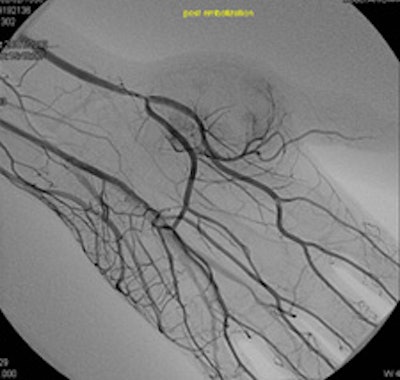

Nuclear medicine, with whom we work closely, has a PET/CT system that incorporates 64-detector-row CT, and has its own cyclotron. We also have two rooms for interventional radiology, and a new area is likely to open in summer 2013 in which vascular surgeons, cardiologists, and radiologists will work together in hybrid rooms. The idea is to have four new rooms, and we are really hoping this will go ahead.

Bilbao and his colleagues are shown in the angiography suite at Clínica Universidad de Navarra.How are Spain's well-documented economic difficulties affecting you?